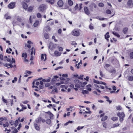

We implemented our algorithm using the Python Optimal Transport (POT) library 222https://github.com/rflamary/POT which include GPU-accelerated versions of Sinkhorn regularization. We used Nvidia GeForce RTX 2080 Ti for our experiments. Pytorch framework was used for StainGAN 333https://github.com/xtarx/StainGAN and CNN3 444https://github.com/neerajkumarvaid/Nuclei_Segmentation implementations. We evaluated our approach against Reinhard et al. [12], Macenko et al.[7], Khan et al. [4], Vahadne et al. [17], and StainGAN [14].

| Source | Reinhard[12] | Macenko[7] | Khan[4] | Vahadane[17] | StainGAN[14] | (Ours) | (Ours) | Target |

|---|---|---|---|---|---|---|---|---|

4.1 Stain Normalization Evaluation

We used MITOS-ATYPIA’14 challenge dataset for evaluating our stain normalization. The dataset includes same tissue sections scanned by two different scanners (Aperio-A and Hamamatsu-H) with total 424 X20 A-H frame pairs, 300 training and 124 testing. Images from scanner A are normalized and matched against the real corresponding images from H (ground truth). As in StainGAN [14], 10,000 random (256256) patches from 300 training frames were used for training (26 epochs with the regularization parameter , learning rate 0.0002, Adam optimizer with a batch size of 4) and 500 patches from 124 testing data used for evaluation. The visual and quantitative comparisons are shown in Figure 3 and Table 1, respectively. For the traditional case (one reference and source), our results are very similar to Reinhard et al. [12] since they also do color matching in Lab space, but our results improve drastically given two reference images. The references in our case span patches with different amounts of background visible. We also tested with different reference images and we show that we get a tighter bound as long as the references contain different amounts of background visibility; see Figure 4 for the box plots of SSIM for different references.